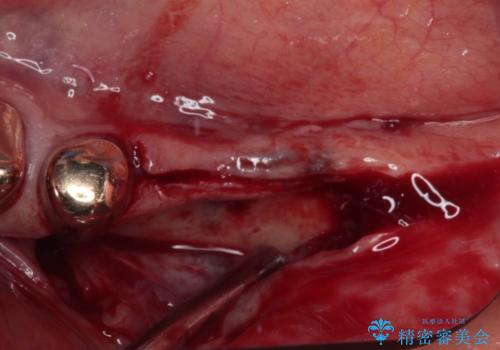

レントゲンやCTより、骨の高さと幅が不足しており、骨を増やす必要のある状態でした。

しかしながら、全身疾患により骨造成術の予後に不安があったため、デンサーバー(Densah ® Bur)という骨幅を増大することが可能なドリルを用いてインプラントを埋入することとしました。

インプラント埋入後、必要以上に傷口に歯ブラシを当てすぎてしまったことで歯肉の炎症が続き、それに伴いインプラント周辺の骨が若干吸収してしまいました。それでも術後の経過は良好で、違和感や不具合なく使用できています。